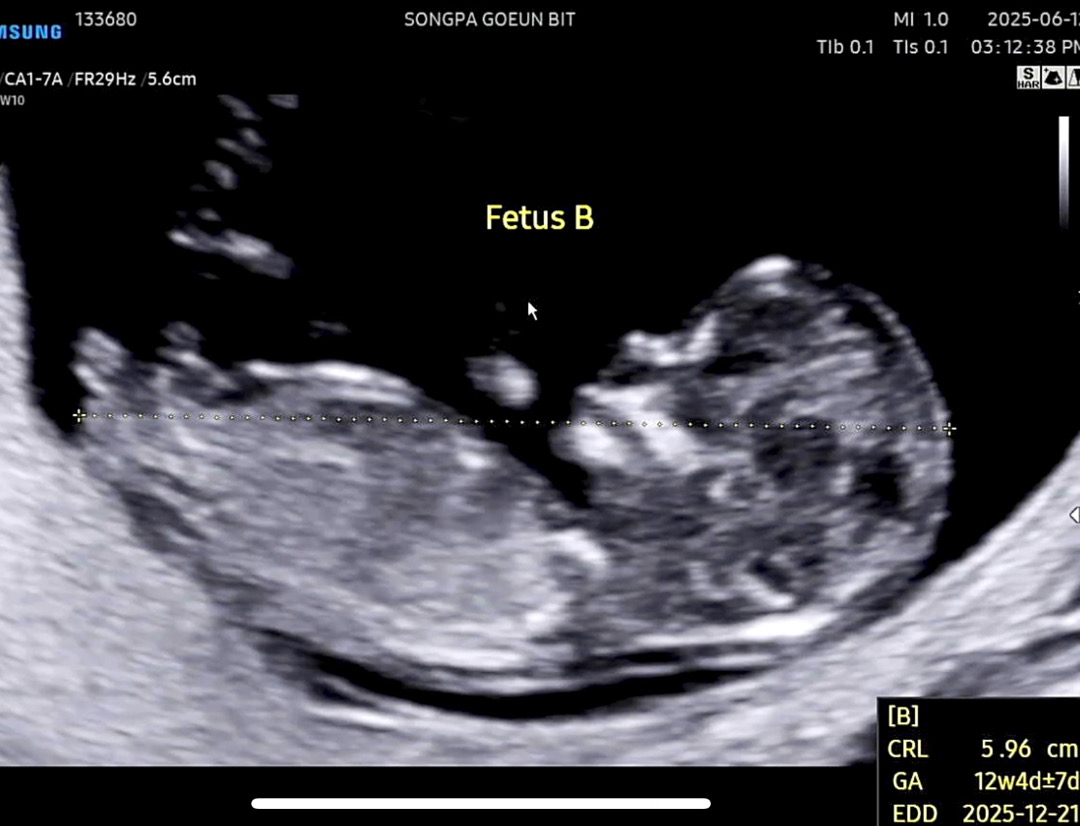

쌍둥이 12주차 각도법좀 봐주세욤😳 B

쌍둥이 오늘 12주차 초음파 보고왔네요^^; 음.. 각도법상 둘이 너무 다른느낌이긴한데.. 확인 부탁드려요🧐

아들 각도 같아요.

아들에한표요~!!